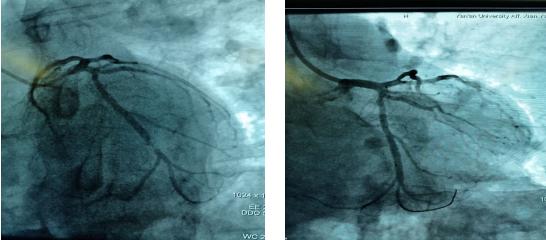

吳醫生迅速到達心電圖室,查看患者意識不清,心電圖提示下壁心肌梗死、三度房室傳導阻滯。立即給予阿托品、異丙腎上腺素提升心率,經積極搶救后患者心律逐漸恢復,意識逐漸清醒。“考慮患者是突發急性心梗引起的惡性心律失常,猝死風險極高,必須行急診介入手術”,李新國責任總醫師告知家屬病情,同時啟動應急預案,通知導管室做好急診手術準備,應急電梯待命…家屬同意手術后,立即前往導管室,實施急診冠脈造影手術。造影結果證實LCX中遠段95%狹窄,術中于病變血管處植入支架1枚,術后血流恢復,患者癥狀改善。在10余名醫護人員3個多小時的緊急搶救下,終于我們戰勝了死神。這一天,許久未晴的天空、陽光格外晴朗、明媚;這一天,北方的寒冬似乎也有了溫度…